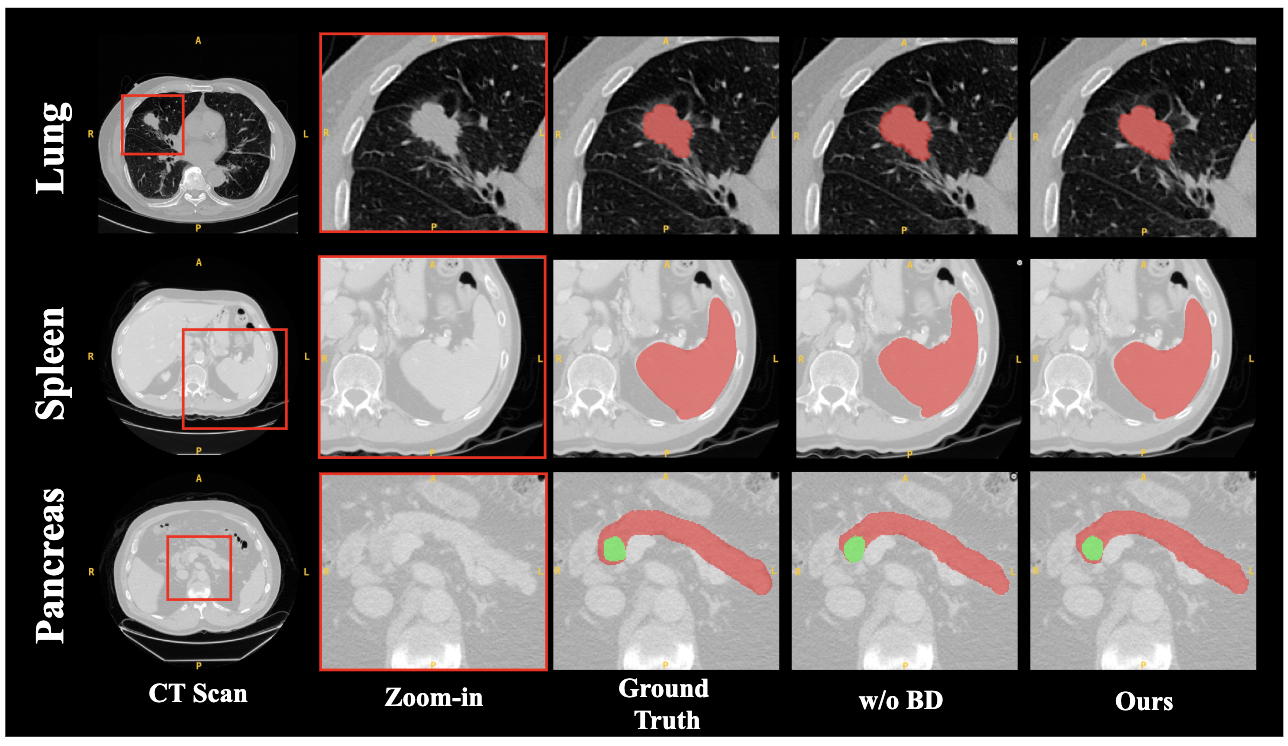

D.3 Effectiveness of BD Module

To validate the effectiveness of our proposed BD module, we designed an experiment comparing our full model with an ablated version that excludes this component (“w/o BD”). The quantitative results, presented in Table 5, highlight the consistent and positive impact of the BD module across all three medical imaging datasets. The most salient improvement is observed in the boundary-sensitive HD95 metric, particularly on the Lung dataset, where it drops dramatically from 9.8799 to 3.5148. Similarly, notable gains in Dice score are achieved on both the Lung (0.7366 to 0.7627) and Pancreas (0.6727 to 0.7039) datasets.

These empirical results and visualization in Fig. 6 strongly validate the design of our BD module. The significant reduction in Hausdorff Distance across the board confirms the module’s efficacy in guiding the network to learn more precise and accurate representations of organ boundaries. By explicitly focusing on the boundary details, our model is able to produce segmentation masks with higher fidelity, which is crucial for downstream clinical applications. Therefore, the BD module serves as an essential component for refining the segmentation results and improving overall performance.

Refer to caption

Figure 6: Visual comparison of segmentation results with and without BD module.